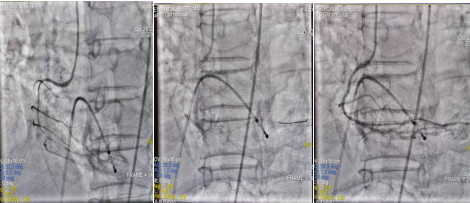

患者徐先生1年前开始无明显诱因下出现胸闷痛不适,活动后加重,于当地村卫生室服用药物治疗后仍有活动后疼痛不适,休息后可缓解,未予重视。10月28日下午16:30患者干农活时突发胸痛不适,上至咽喉部,行心电图示:窦性心动过缓,ST段抬高,考虑“急性下壁ST 段抬高型心肌梗死”,立即予完善术前准备,经过急诊CAG+血栓抽吸+冠脉内溶栓+PPCI术成功把患者从死亡线上拉了回来。

图1 术前前降支造影图2 术前右冠造影

图3 治疗后前降支造影图4 治疗后右冠造影